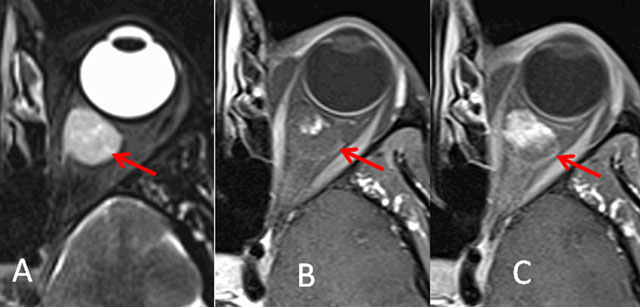

Figure 1

Cavernous hemangioma. Axial T2-weighted (A) and fat-saturated T1-weighted imaging with injection: immediate (B) and delayed (C).